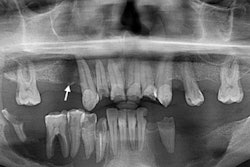

Finally, a panoramic x-ray scan revealed bilateral osteolytic lesions in a man's jaw, leading to the diagnosis and treatment of the rare condition Langerhans cell histiocytosis. An x-ray of the man's mouth taken a couple of years earlier did not show any aggressive alveolar bone destruction or bone loss. However, the most recent x-ray showed geographic bony destruction of the upper jaw and both sides of the lower jaw "with the teeth appearing to float," highlighting the need to perform these routine scans on patients, the authors noted in a fascinating case report.